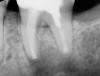

The patient stated that a previous root canal had been performed on tooth No. 18 many years ago, but he had no memory of the exact date or the name of the dentist who provided the treatment. The referring dentist had no records or preoperative radiographs of tooth No. 18 from before the initial endodontic treatment. A limited FOV CBCT scan of the tooth was taken, and a radiolucency was observed on the mesial and distal roots (Figure 4). The pretreatment pulpal diagnosis was "previously treated," and the periradicular diagnosis was symptomatic apical periodontitis.

The clinician determined that the treatment options were conventional endodontic retreatment or endodontic surgery, which would involve resectioning of the mesial and distal roots, preparation of the root ends, and placement of a bioceramic root-end filling. With regard to restorative evaluation, the existing crown on tooth No. 18 was deemed to be within normal limits. Although the periapical radiograph (Figure 3) showed a radiolucent line around the distal portion of the crown, the marginal integrity was determined to be clinically acceptable. The CBCT demonstrated that the inferior alveolar nerve canal was close in proximity to the mesial and distal roots of tooth No. 18. Also, clinically the surgical access around tooth No. 18 was limited for root-end resection endodontic surgery. The axial CBCT view showed that the current canal obturation was within normal limits (Figure 5).

CBCT sagittal view (lingual view exposure) of tooth N o. 18 revealed mesial

and distal root periapical radiolucency.

Fig 4.

CBCT axial view of tooth

No. 18 revealed canal obturation within normal limits.

Fig 5.